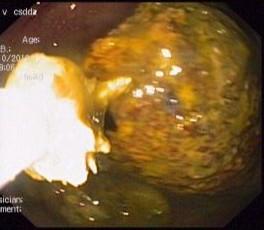

通过会诊评估,李大威医生建议患者通过胃镜进行取石。在进行了完备的术前检查后,消化内科主治医师李大威在护士张令、麻醉医师王鹏程的协助下为患者施行了“无痛胃镜下胃柿石碎石及取石术”。胃镜进入胃腔后,可见一块约4.0cm×4.5cm大小的黄色可移动柿石,并伴有溃疡。此时确诊为:胃柿石、胃溃疡。

李大威医师在尝试使用圈套器将其套住取出时发现,由于柿石过大,无法通过贲门取出。遂用碎石网篮分次分割柿石,化整为零,应用网兜分次取出。历时50分钟后,患者胃内柿石被全部取出。患者不适症状也得到缓解。